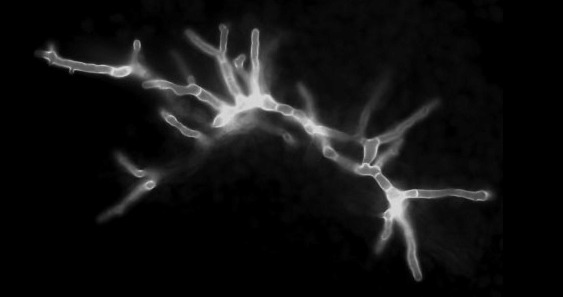

- Histopathology: Wide (6-16 μm), ribbon-like, pauciseptate hyphae with right-angle branching